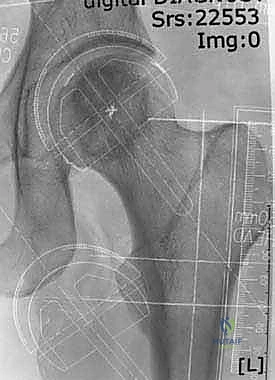

تعتبر هذه الجراحة من أدق جراحات العظام، ويقوم بها الأستاذ الدكتور محمد هطيف بخطوات منهجية دقيقة تضمن أعلى معدلات النجاح:

3. نحت وتشكيل رأس عظمة الفخذ

بدلاً من قطع الرأس، يستخدم الجراح أدوات ميكروسكوبية ومثاقب دقيقة جداً لإزالة الغضروف التالف وطبقة رقيقة من العظم المريض، ليتم "نحت" رأس العظمة ليصبح جاهزاً لاستقبال الغطاء المعدني بشكل مثالي.

4. تركيب الغطاء المعدني (Femoral Component)

يتم تثبيت التاج أو الغطاء المعدني الأملس فوق رأس عظمة الفخذ المنحوت، وغالباً ما يتم تثبيته باستخدام مادة أسمنتية طبية خاصة لضمان ثباته المطلق.

5. تحضير وتلبيس تجويف الحُق (Acetabular Component)

يتم تنظيف تجويف الحوض (الحُق) من الغضاريف المتآكلة باستخدام مبشرة طبية، ثم يزرع وعاء معدني (Cup) داخل التجويف. هذا الوعاء يثبت عادة عن طريق الضغط (Press-fit) حيث ينمو العظم الطبيعي لاحقاً حوله ليثبته بقوة.